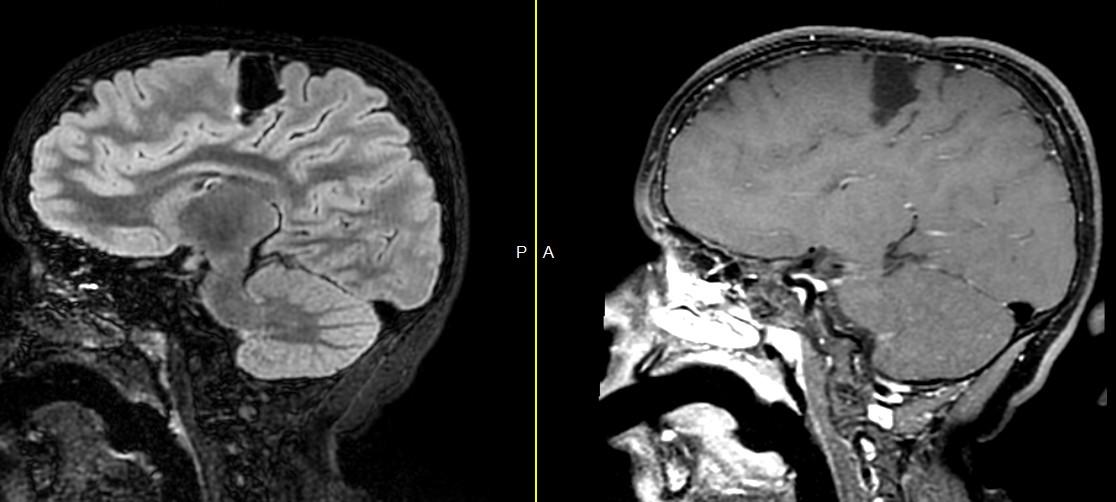

Hemorrhagic

Stroke:

Hemorrhagic Venous Infarction

Thanks to H. Rowley